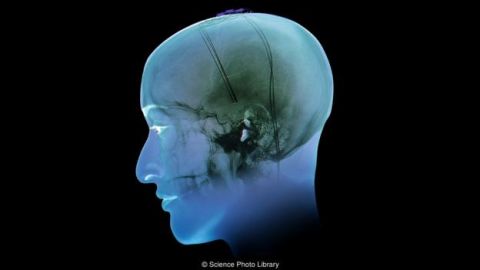

Cómo unos electrodos pueden ayudar a tratar la obesidad y la depresión

La estimulación cerebral profunda mostró beneficios inesperados contra la obesidad. ¿En qué consiste el tratamiento?

SCIENCE PHOTO LIBRARY Crédito: Science Photo Library

Como tratamiento de último recurso, los psiquiatras tomaron una decisión drástica. Decidieron instalarle en el cerebro un dispositivo eléctrico. Se trataba de una terapia invasiva conocida como estimulación cerebral profunda.

Este tratamiento ya se usa con frecuencia para aliviar los síntomas del Parkinson y la epilepsia.